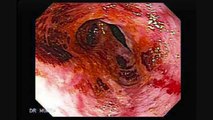

Sabias que gran parte de los problemas de salud se originan por un colon tóxico? Y como intoxicamos nuestro colon?<br />Sufres de gastritis, estreñimiento, reflujo, agriera, colon irritable, tienes problemas de manchas en la piel, te duele frecuentemente la cabeza o has tratado de bajar de peso y no lo logras?<br />Mira este vídeo y conoce un poco más de tu cuerpo y como la salud de tu colon esta más relacionada con tu salud de lo que crees!<br />Si quieres conocer como solucionarlo, escríbenos a "claudiayjuanhlf@gmail.com" sin importar el pais donde vivas, cuéntanos tu problema y te diremos como te podemos ayudar-.